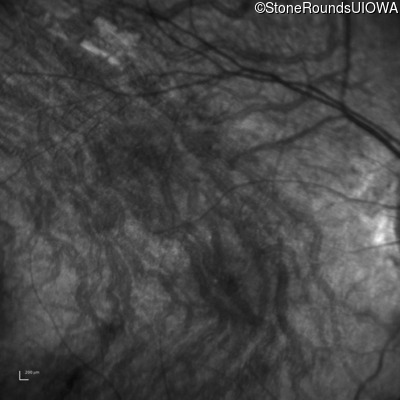

Infrared Fundus Photograph - Right - 10/300 sc

Exemplar